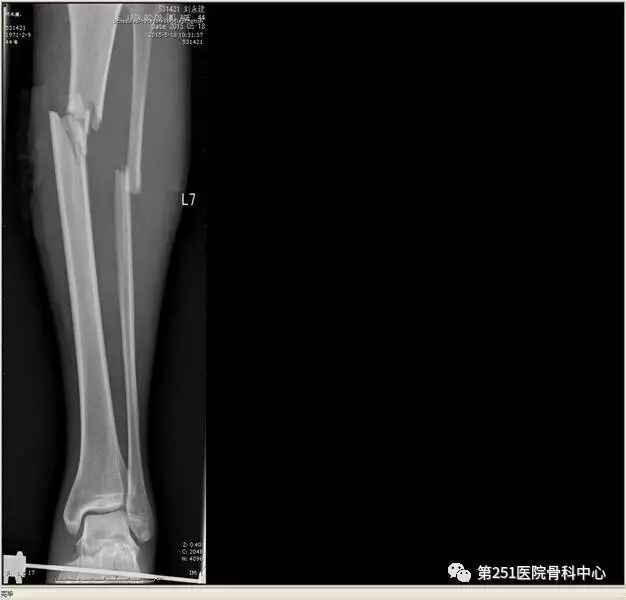

病例1:男性,40岁,车祸伤,胫腓骨多段骨折。